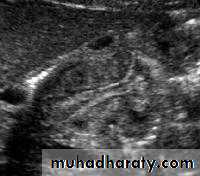

Pyloric stenosis is relatively common and has a male predilection (M:F ~ 4:1), and is more commonly seen in Caucasians 4. It typically occurs between the 4-8 weeks of life. There may be a positive family history. Incidence of hypertrophic pyloric stenosis is approximately 2-5 per 1,000 births per year in most white populations,Hypertrophic pyloric stenosis refers to idiopathic thickening of gastric pyloric musculature which then results in progressive gastric outlet obstruction

In a normal situation, the pyloric muscle thickness (diameter of a single muscular wall on a transverse image) should normally be less than 3 mm (most accurate 3) and the length (longitudinal measurement) should not exceed 15 mm.